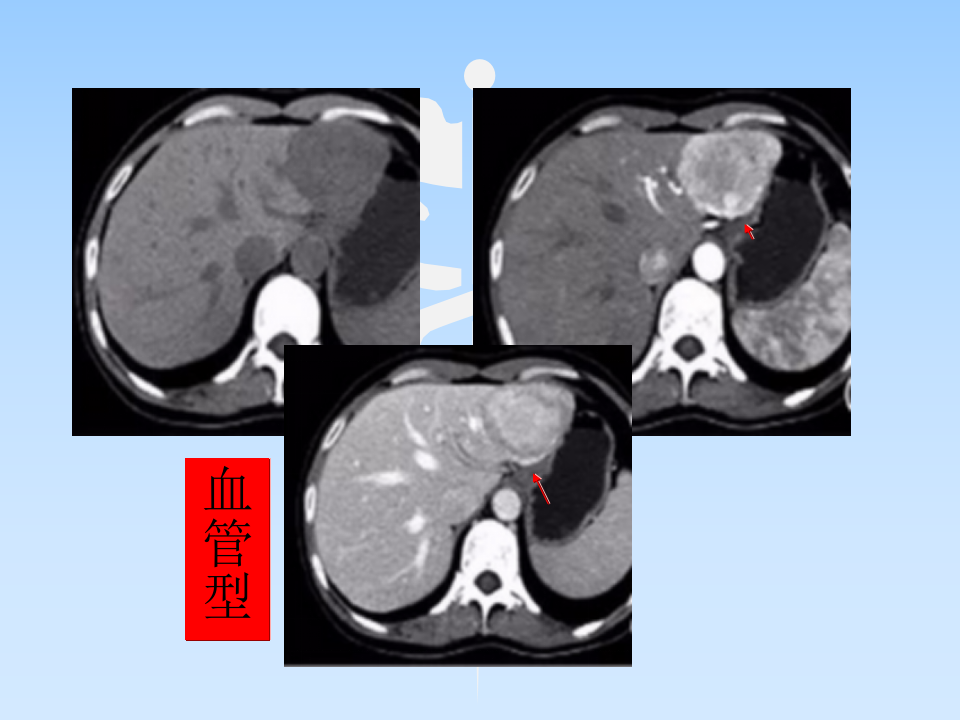

肝AML授课--曾蒙苏.ppt